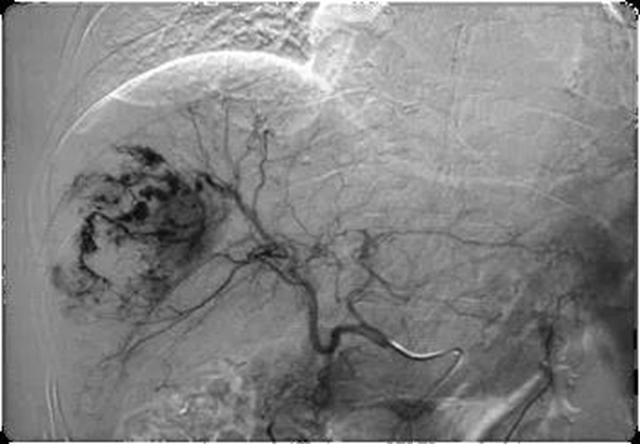

肝动脉灌注化疗栓塞术(TACE)

是将导管选择性插入到肿瘤供血靶动脉后,以适当的速度注入适量的栓塞剂,使靶动脉闭塞,引起肿瘤组织的缺血坏死。